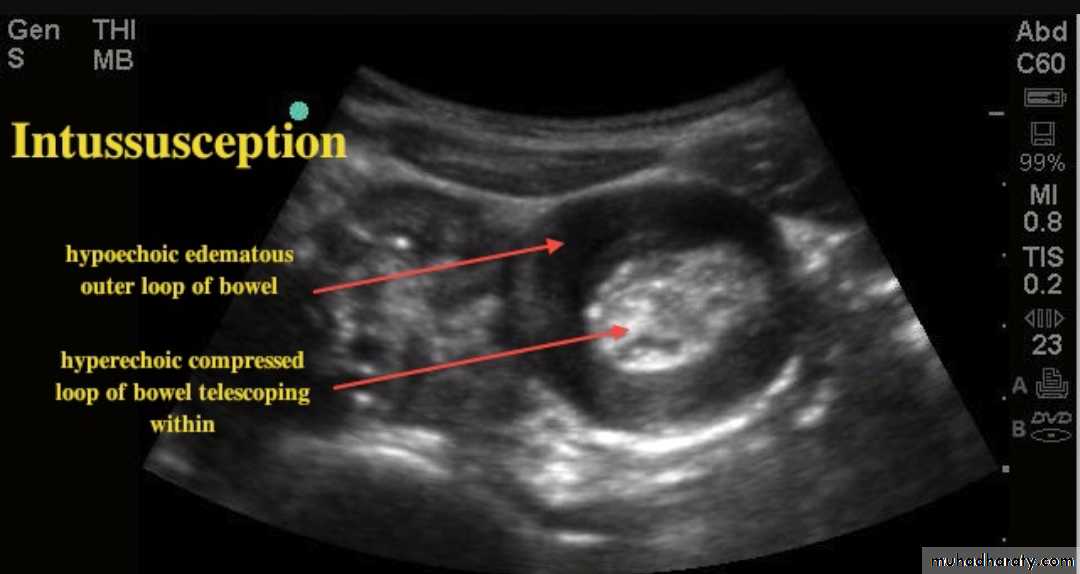

Ultrasound

is a reliable screening tool for children at low risk for intussusceptionsUltrasound signs include:

target sign (also known as the doughnut sign)

Pseudo kidney shape sign